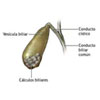

Colelitíase

A vesícula é uma pequena saculação ( como uma bexiga murcha) que se encontra junto ao fígado e sua função é armazenar bile, um líquido amarelo esverdeado espesso produzido pelo fígado . Após se alimentar , a vesícula se espreme liberando bile em grande quantidade no intestino para entrar em contato com o alimento e continuar o processo de digestão iniciado pelo estômago. A função básica da bile é digerir as gorduras. Saiba mais Hemorragia digestiva alta e baixa